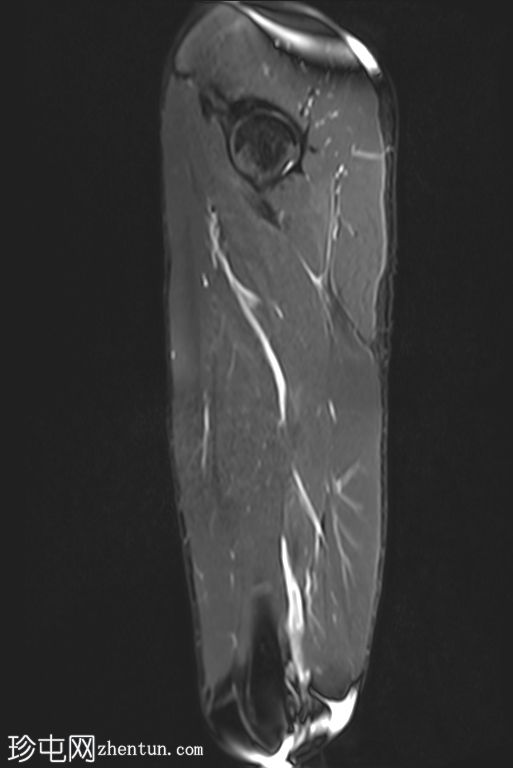

矢状位

T1 tirm

收肌长肌腱从耻骨起点完全撕脱,可见充满液体的间隙(4毫米),肌腱近端回缩。

相关的肌内水肿累及收肌长肌、短肌和耻骨肌,筋膜间液沿股薄肌向内侧延伸。

MRI 表现与收肌长肌腱从起点撕脱并远端回缩相符,可见充满液体的间隙、筋膜间液和肌肉拉伤。

根据英国田径协会肌肉损伤分类(BAMIC),该损伤被归类为 4c 级。